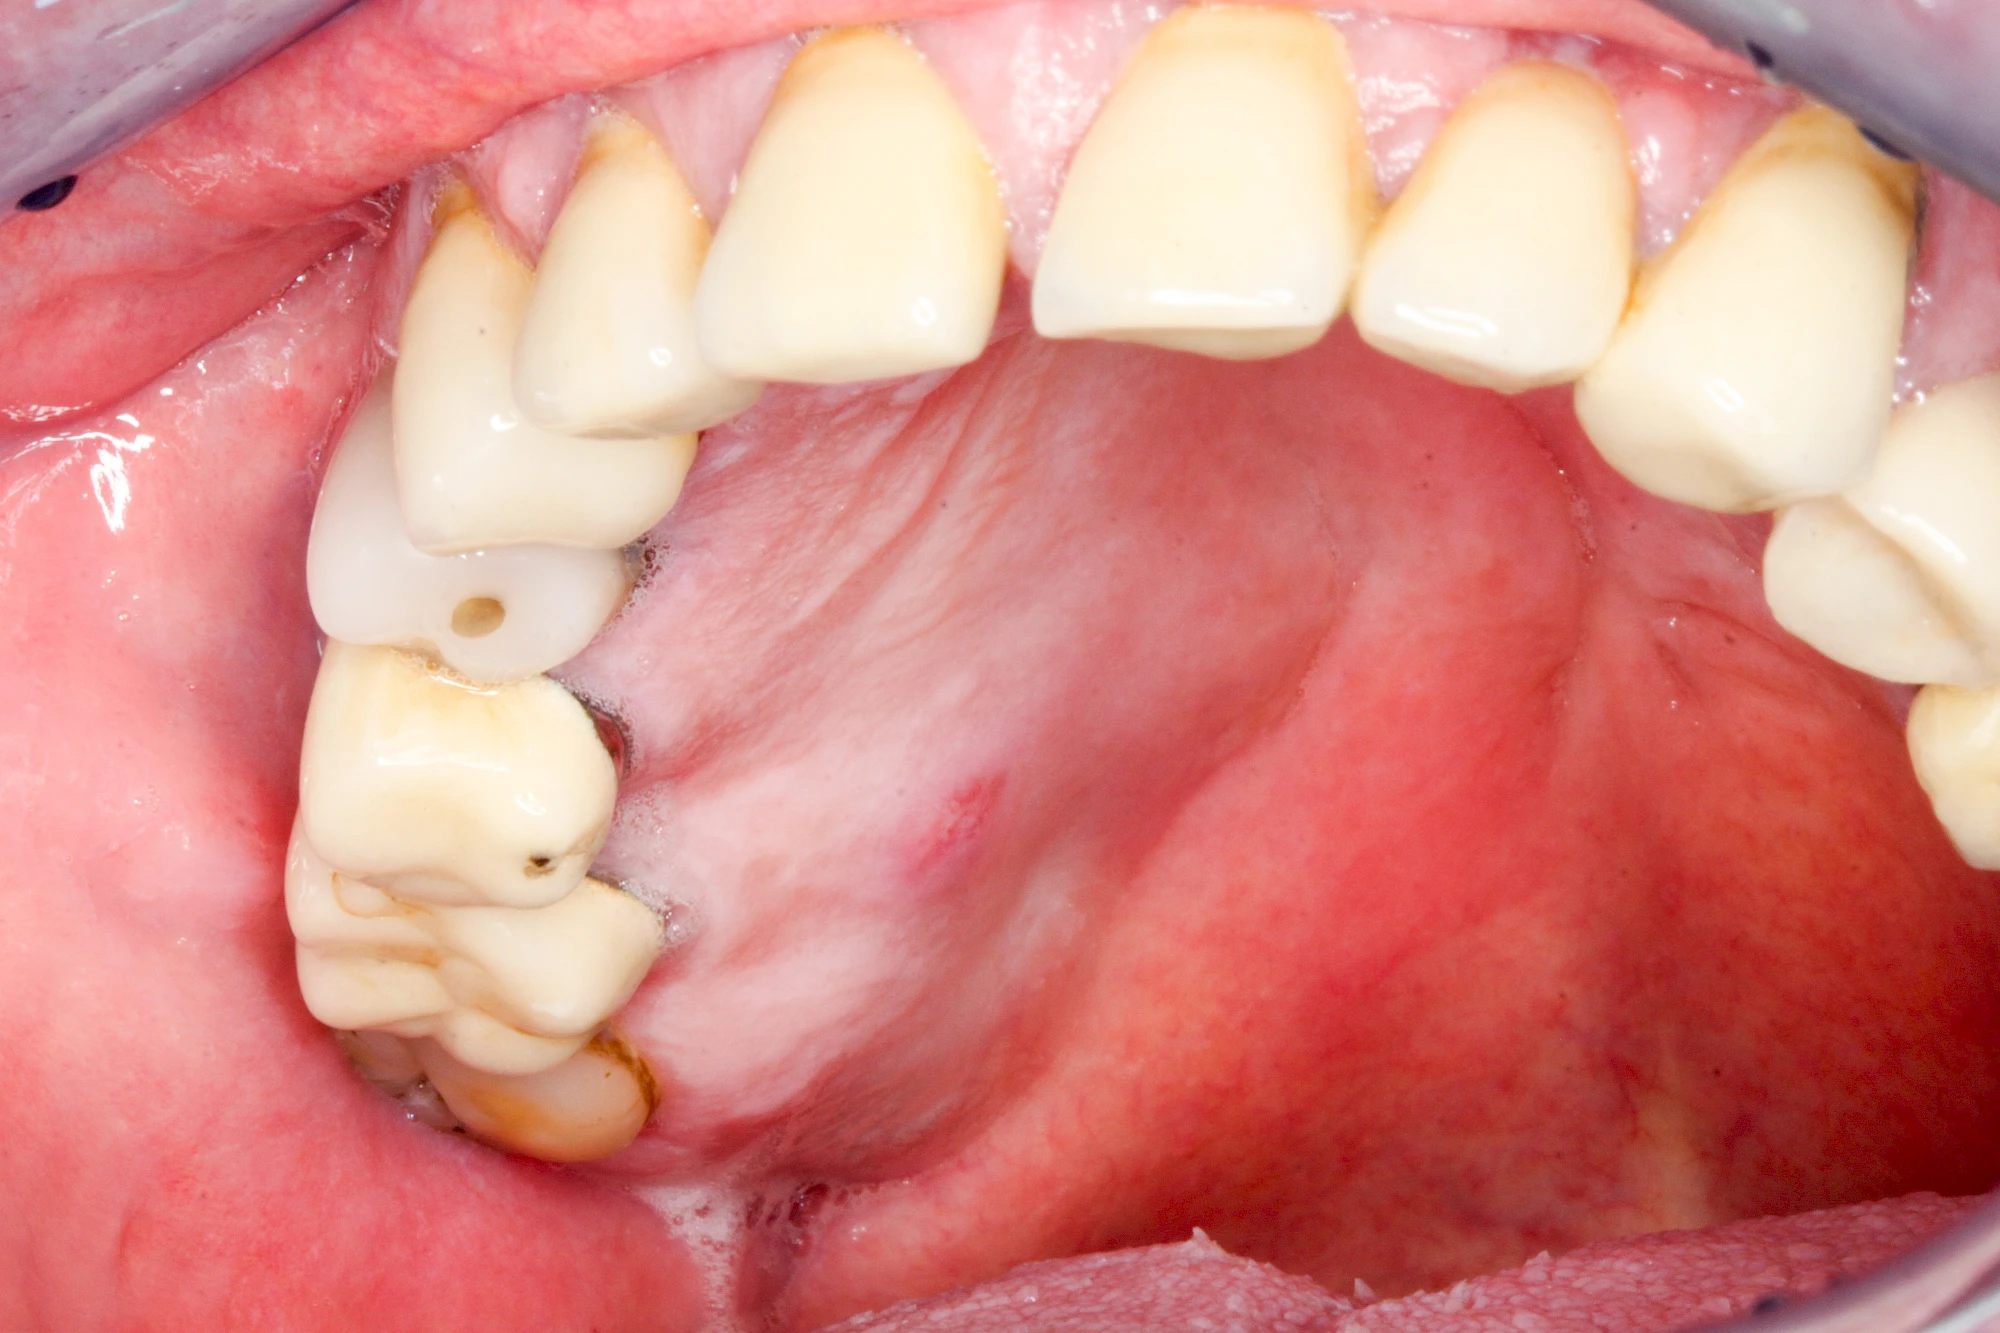

Ist zunächst nur das Zahnfleisch von der Entzündung betroffen, spricht man von Gingivitis. Später, wenn auch der Knochen um die Zähne herum entzündet ist, spricht man von einer Parodontitis. Bei der Parodontitis wird der Knochen nach und nach abgebaut und das Zahnfleisch zieht sich zurück. Die Zahnhälse und Zahnwurzeloberflächen liegen mehr und mehr frei. Die Zähne werden zunehmend lockerer und fallen schließlich aus.

Bei Implantaten – also operativ eingebrachten künstlichen Zahnwurzeln – kann der Körper die Bakterien auch nicht so gut abwehren. Hier spricht man im Fall einer Entzündung von einer Peri-Implantitis, also einer Entzündung um das Implantat herum.